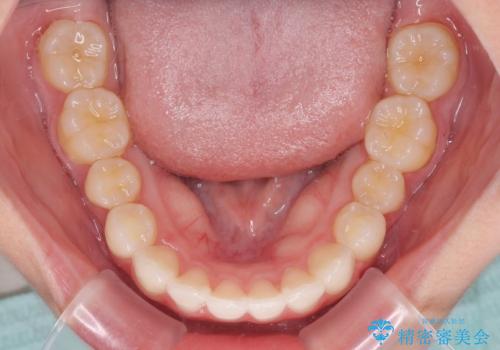

- 前歯2本が飛び出してることを気にして来院された患者様です。

全体的に黄ばんだ歯の色も気になるとのことで、マウスピース矯正により飛び出した前歯を治しつつ、ホームホワイトニングを併用して黄ばみを解消していくこととしました。

歯と歯の間を削ることで、飛び出した前歯が引っ込み、スッキリとした口元となりました。

歯の黄ばみも改善され、明るい歯並びとなりました。